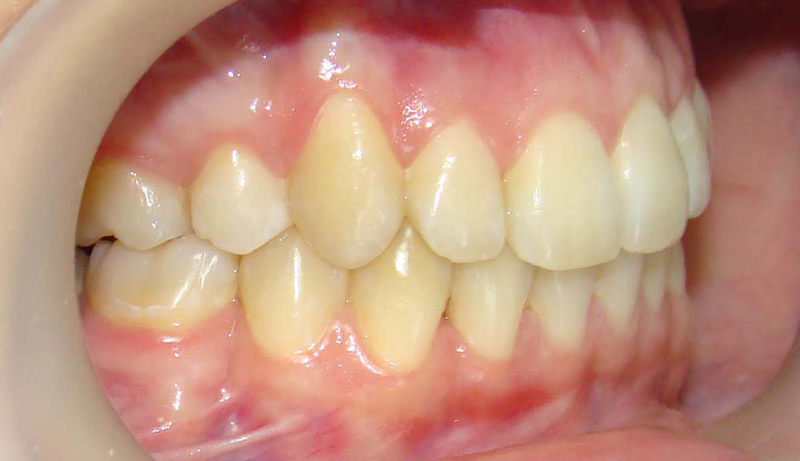

А это уже молодой человек 10 лет. Тоже получилось справиться без удаления. Хоть оно и было показано. Но мальчик очень упорно носил специальные аппаратики и резиночки. Покажу со всех сторон. Этот случай победил в конкурсе на конференции